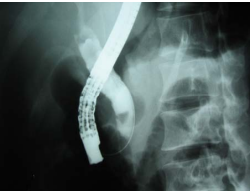

Hình 4. Chụp đường mật qua da và qua nhu mô gan

(Nguồn: www.centerspan.org/pubs/liver/diamond1.htm)